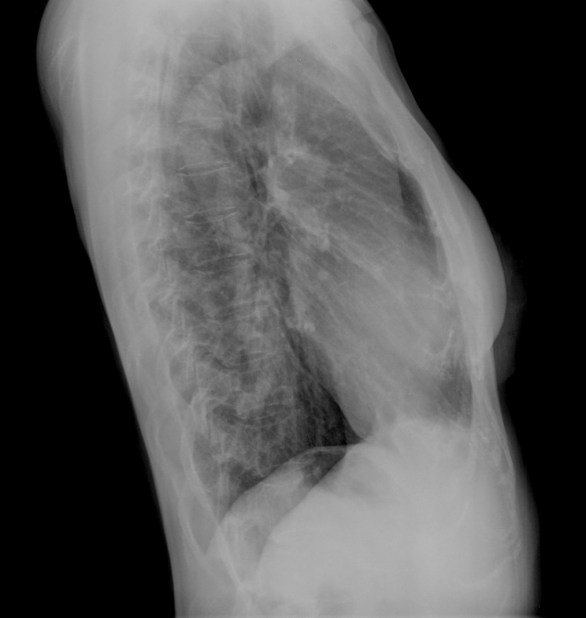

CASO: Febrícula y tos de 4 días de evolución.

Hallazgos:

- En la placa PA se observa una asimetría en los hilios pulmonares, el hilio izquierdo tiene una densidad aumentada.

- Tras examinar la placa lateral se observa un aumento de densidad en la columna que puede ser compatible con una condensación, es el signo de la desnificación vertebral.

SIGNO DE LA DENSIFICACIÓN VERTEBRAL: En la radiografía lateral normal, la densidad de la columna torácica tiende a disminuir desde la parte superior hasta el diafragma; la alteración de ese patrón por la presencia de una densidad superpuesta a la columna, indica la existencia de una consolidación pulmonar. Este signo adquiere especial valor cuando en la proyección posteroanterior la consolidación está oculta en el espacio retrocardíaco o en la base pulmonar.